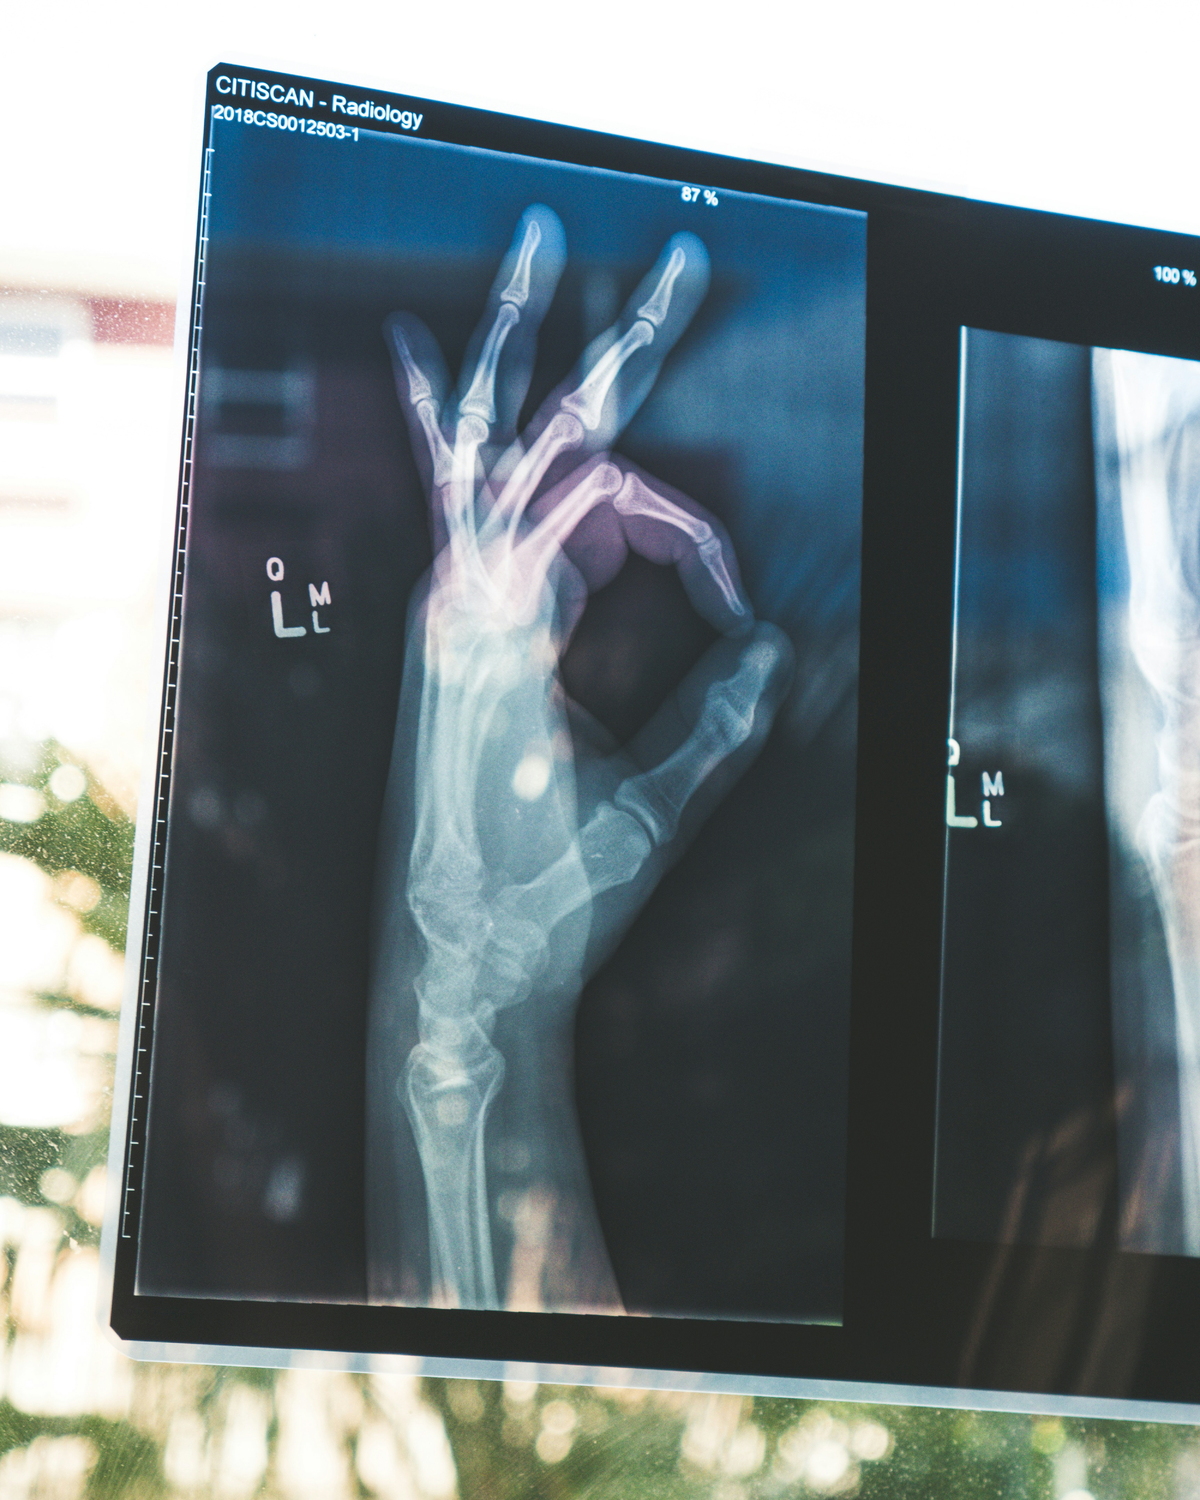

25일 오전, 서울 강남구의 한 건강검진센터. 차가운 금속판 앞에 서서 숨을 크게 들이마신다. “참으세요”라는 안내 방송과 함께 ‘띠리릭’ 소리가 울리면 상황은 끝난다.

감기 기운에 들른 내과부터 발목을 삐끗해 찾은 정형외과, 매년 돌아오는 직장인 건강검진까지 우리는 1년에도 몇 번씩 이 익숙한 풍경 속으로 들어간다. 너무 흔해서 가끔 잊지만, 이 기계의 정체는 ‘방사선 촬영장치’다.

세계보건기구(WHO) 자료에 따르면 흉부 엑스레이 1회 촬영 시 노출되는 방사선량은 약 0.02~0.1mSv다. 치과 엑스레이는 0.005~0.01mSv, 복부 CT는 5~10mSv 수준이다.

흉부 엑스레이 한 번은 일상에서 며칠간 자연 상태로 노출되는 방사선량과 비슷한 범위로 알려져 있다. 단일 촬영의 위험 자체는 매우 낮은 편이다.